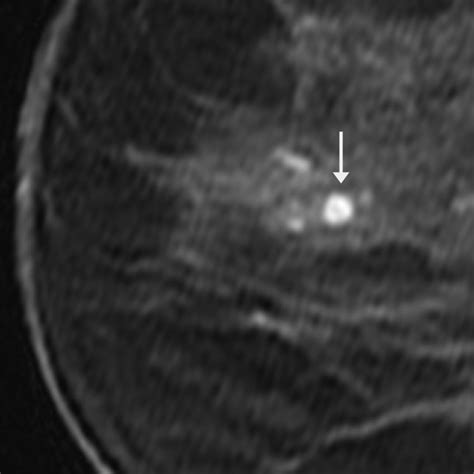

Because clinical examination alone cannot definitively distinguish a benign papilloma from other breast conditions, including breast cancer, imaging and diagnostic procedures are required. A breast specialist will typically follow a systematic approach to diagnosis:

Mammography Screening or diagnostic imaging to visualize the internal structure of the breast.

Breast Ultrasound High-resolution imaging used to evaluate lumps and look inside the ducts for abnormal growth.